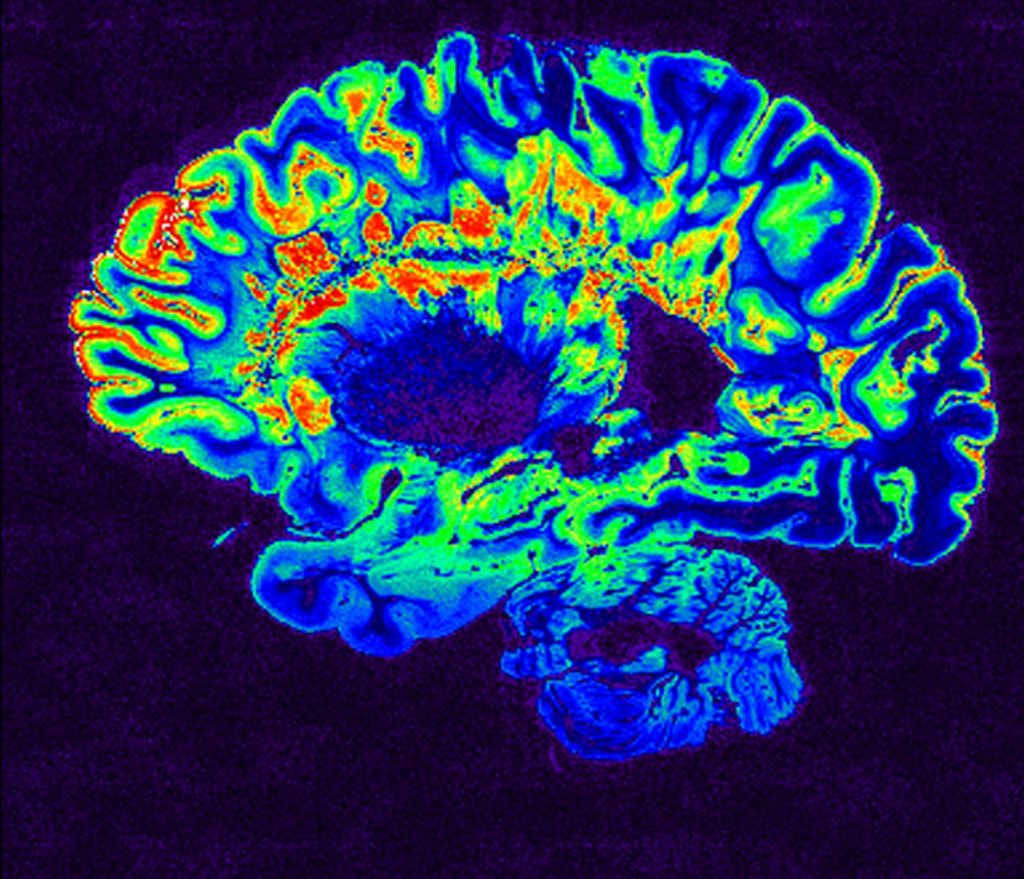

Με την χρήση της μαγνητικής τομογραφίας γίνεται ολοένα και γρηγορότερη διάγνωση της πάθησης, με αποτέλεσμα η φυσική εξέλιξη της νόσου να μην υπερβαίνει τους έξι μήνες.